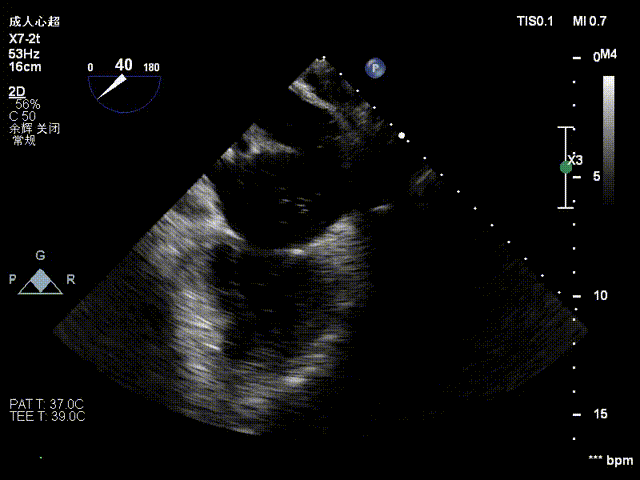

患者取平卧位,消毒铺巾后,穿刺右股静脉后置入6F血管鞘,经食道超声指导下进行房间隔穿刺,穿刺高度约4cm。

房间隔穿刺高度4cm

房间隔穿刺